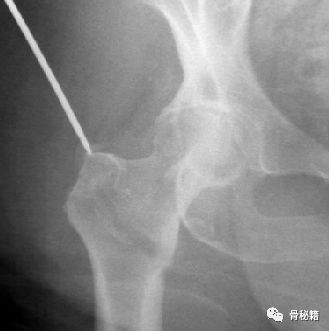

5.最后再通过螺钉的加压完成最后加压

术后影像,是不是感觉不错呢??